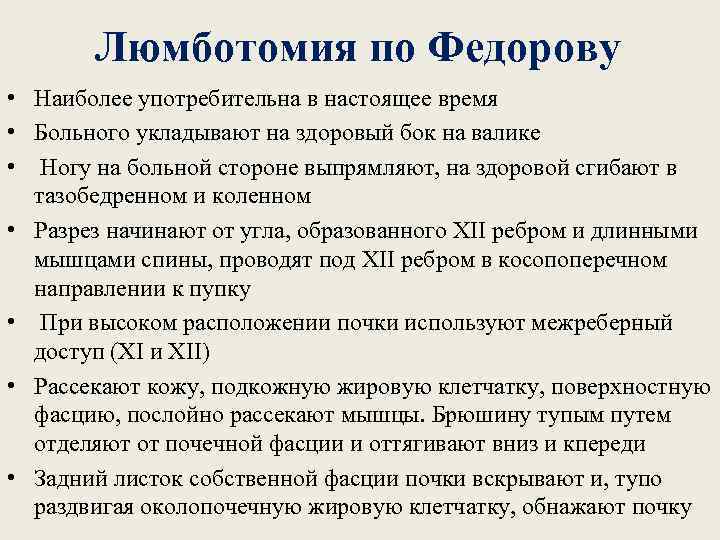

Люмботомия по Федорову • Наиболее употребительна в настоящее время • Больного укладывают на здоровый бок на валике • Ногу на больной стороне выпрямляют, на здоровой сгибают в тазобедренном и коленном • Разрез начинают от угла, образованного XII ребром и длинными мышцами спины, проводят под XII ребром в косопоперечном направлении к пупку • При высоком расположении почки используют межреберный доступ (XI и XII) • Рассекают кожу, подкожную жировую клетчатку, поверхностную фасцию, послойно рассекают мышцы. Брюшину тупым путем отделяют от почечной фасции и оттягивают вниз и кпереди • Задний листок собственной фасции почки вскрывают и, тупо раздвигая околопочечную жировую клетчатку, обнажают почку